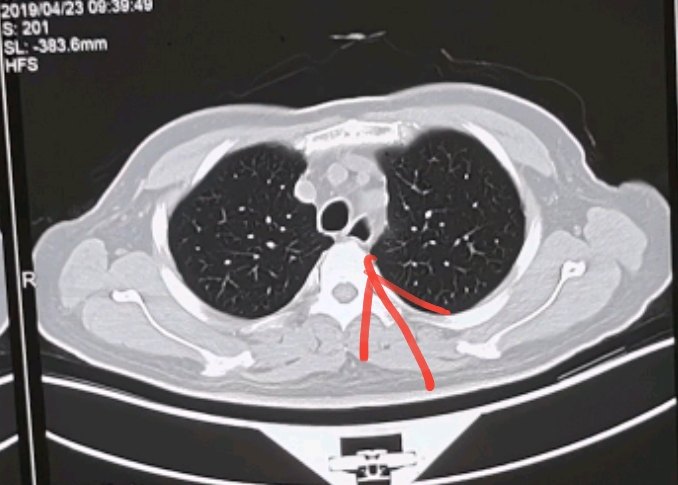

气管憩室,你诊断对了吗?

下面是一些典型憩室ct表现的分享:总结一下,气管憩室,是良性的先天性